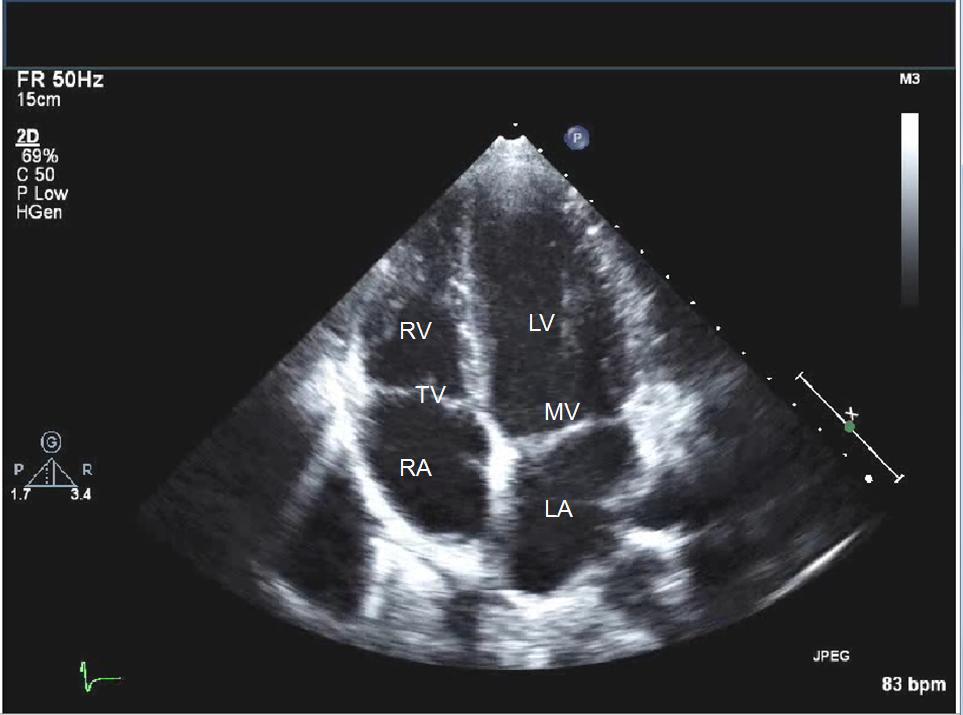

TELE REPORTING ECHO SOFTWARE

KALPAK has developed web based , internet based reporting software for cardiologist to report ECHO from anywhere in the world. The images and the videos are uploaded to the portal , and the reporting doctor accesses these images and videos for examination and based on the findings by the doctor a detailed ECHO report is generated. The report informs you about the present conditions of 4 chambers namely left ventricle, right ventricle, left atrium and right atrium. The conditions of 4 valves mainly mitral valve, pulmonary valve, tricuspid valve and aortic valve is also available in this report. Besides this LV motion diagram is available with the markings of all the 17 segments. Report on aorta, pulmonary artery , IVC, Pulmonary vein, Pericardium, left ventricular function, right ventricular function, pericardial effusion, intracardiac clots, intercardiac tumor, interatrial septum , interventricular septum, ejection fraction etc is available which is based on the images and videos of the heart.